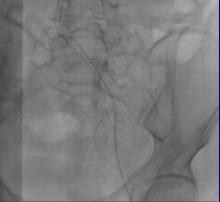

溶栓治疗后复查:

髂股静脉血栓大部分溶解,显示左髂静脉受压情况(Cockett综合征),见图5

图5